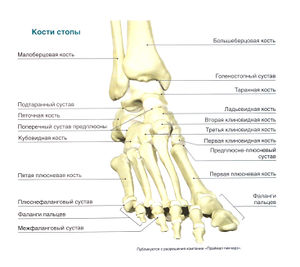

Стопа содержит 26 костей, которые образуют многочисленные суставы. Таранная и пяточная кости объединяются в подтаранный сустав. Пяточная, кубовидная и таранная кости вместе с ладьевидной костью составляют поперечный сустав пред плюсны. Пять плюсневых костей, соединяясь своими основаниями с костями предплюсны (а именно, с кубовидной и клиновидной костями), образуют предплюсне-плюсневые суставы, а головки плюсневых костей вместе с фалангами пальцев образуют плюснефаланговые суставы. Кости каждого пальца соединяются межфаланговыми суставами: на большом пальце стопы этот сустав один, а на остальных —два: проксимальный и дистальный. Суставы стопы укреплены множеством мелких связок.